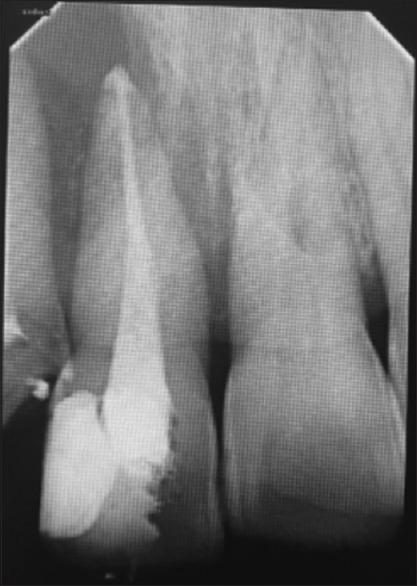

Plasmacytoid mucositis is a rare form of periodontal disease characterized by the infiltration of plasma cells into the gingival tissues. This case report highlights a unique case of plasmacytoid mucositis with periodontal involvement in a young woman. A 32-year-old female presented with gingival hyperplasia and cheilitis. The clinical examination revealed the presence of deep periodontal pockets, severe gingival inflammation, and bone loss. The patient was treated with a combination of nonsurgical periodontal therapy, systemic antibiotics, and oral hygiene instructions. After 2 months of the treatment, the patient showed significant improvement in the clinical parameters. This case report adds to the existing literature on this condition, emphasizing the importance of early diagnosis and prompt treatment. It highlights the need for a multidisciplinary approach involving periodontists, histopathologists, and microbiologists. The lesson to be learned from this case report is that plasmacytoid periodontitis should be considered and a biopsy should be performed to confirm the diagnosis.

浆细胞样黏膜炎是一种罕见的牙周疾病,其特征是浆细胞浸润牙龈组织。本病例报告突出了一名年轻女性患浆细胞样黏膜炎并伴有牙周受累的独特病例。一名32岁女性出现牙龈增生和唇炎。临床检查发现存在深牙周袋、严重牙龈炎症和骨质流失。该患者接受了非手术牙周治疗、全身抗生素治疗和口腔卫生指导相结合的治疗。治疗2个月后,患者的临床参数有显著改善。本病例报告丰富了关于这种疾病的现有文献,强调了早期诊断和及时治疗的重要性。它突出了多学科方法的必要性,涉及牙周病学家、组织病理学家和微生物学家。从本病例报告中应吸取的教训是,应考虑浆细胞样牙周炎,并应进行活检以确诊。